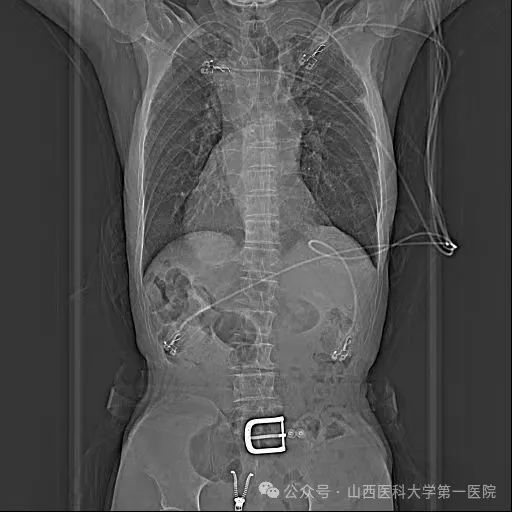

救治未果来到山医大一院进一步诊治。入院完善检查后发现患者属于真正的右位心,即镜面右位心;CT三维重建显示:心脏解剖结构完全相反,后前位下,左心耳位于最右侧。右位心情况大幅提升了手术难度,尤其在房间隔穿刺时,对心房相对毗邻结构的全部重建、穿刺位点选择,都和常规手术大不相同。

胸片示全内脏反转考虑到患者病情特殊,王睿主任医师带领团队进行了详细的术前讨论,结合患者病史、现有检查资料及技术能力、手术安全性等,与患者及家属充分沟通后,制定了手术方案:在Carto3系统下运用心腔内超声导管(ICE)及X线透视指导射频消融及左心耳封堵手术,并对手术可能出现的风险进行了汇总且制定了相应的防范措施。